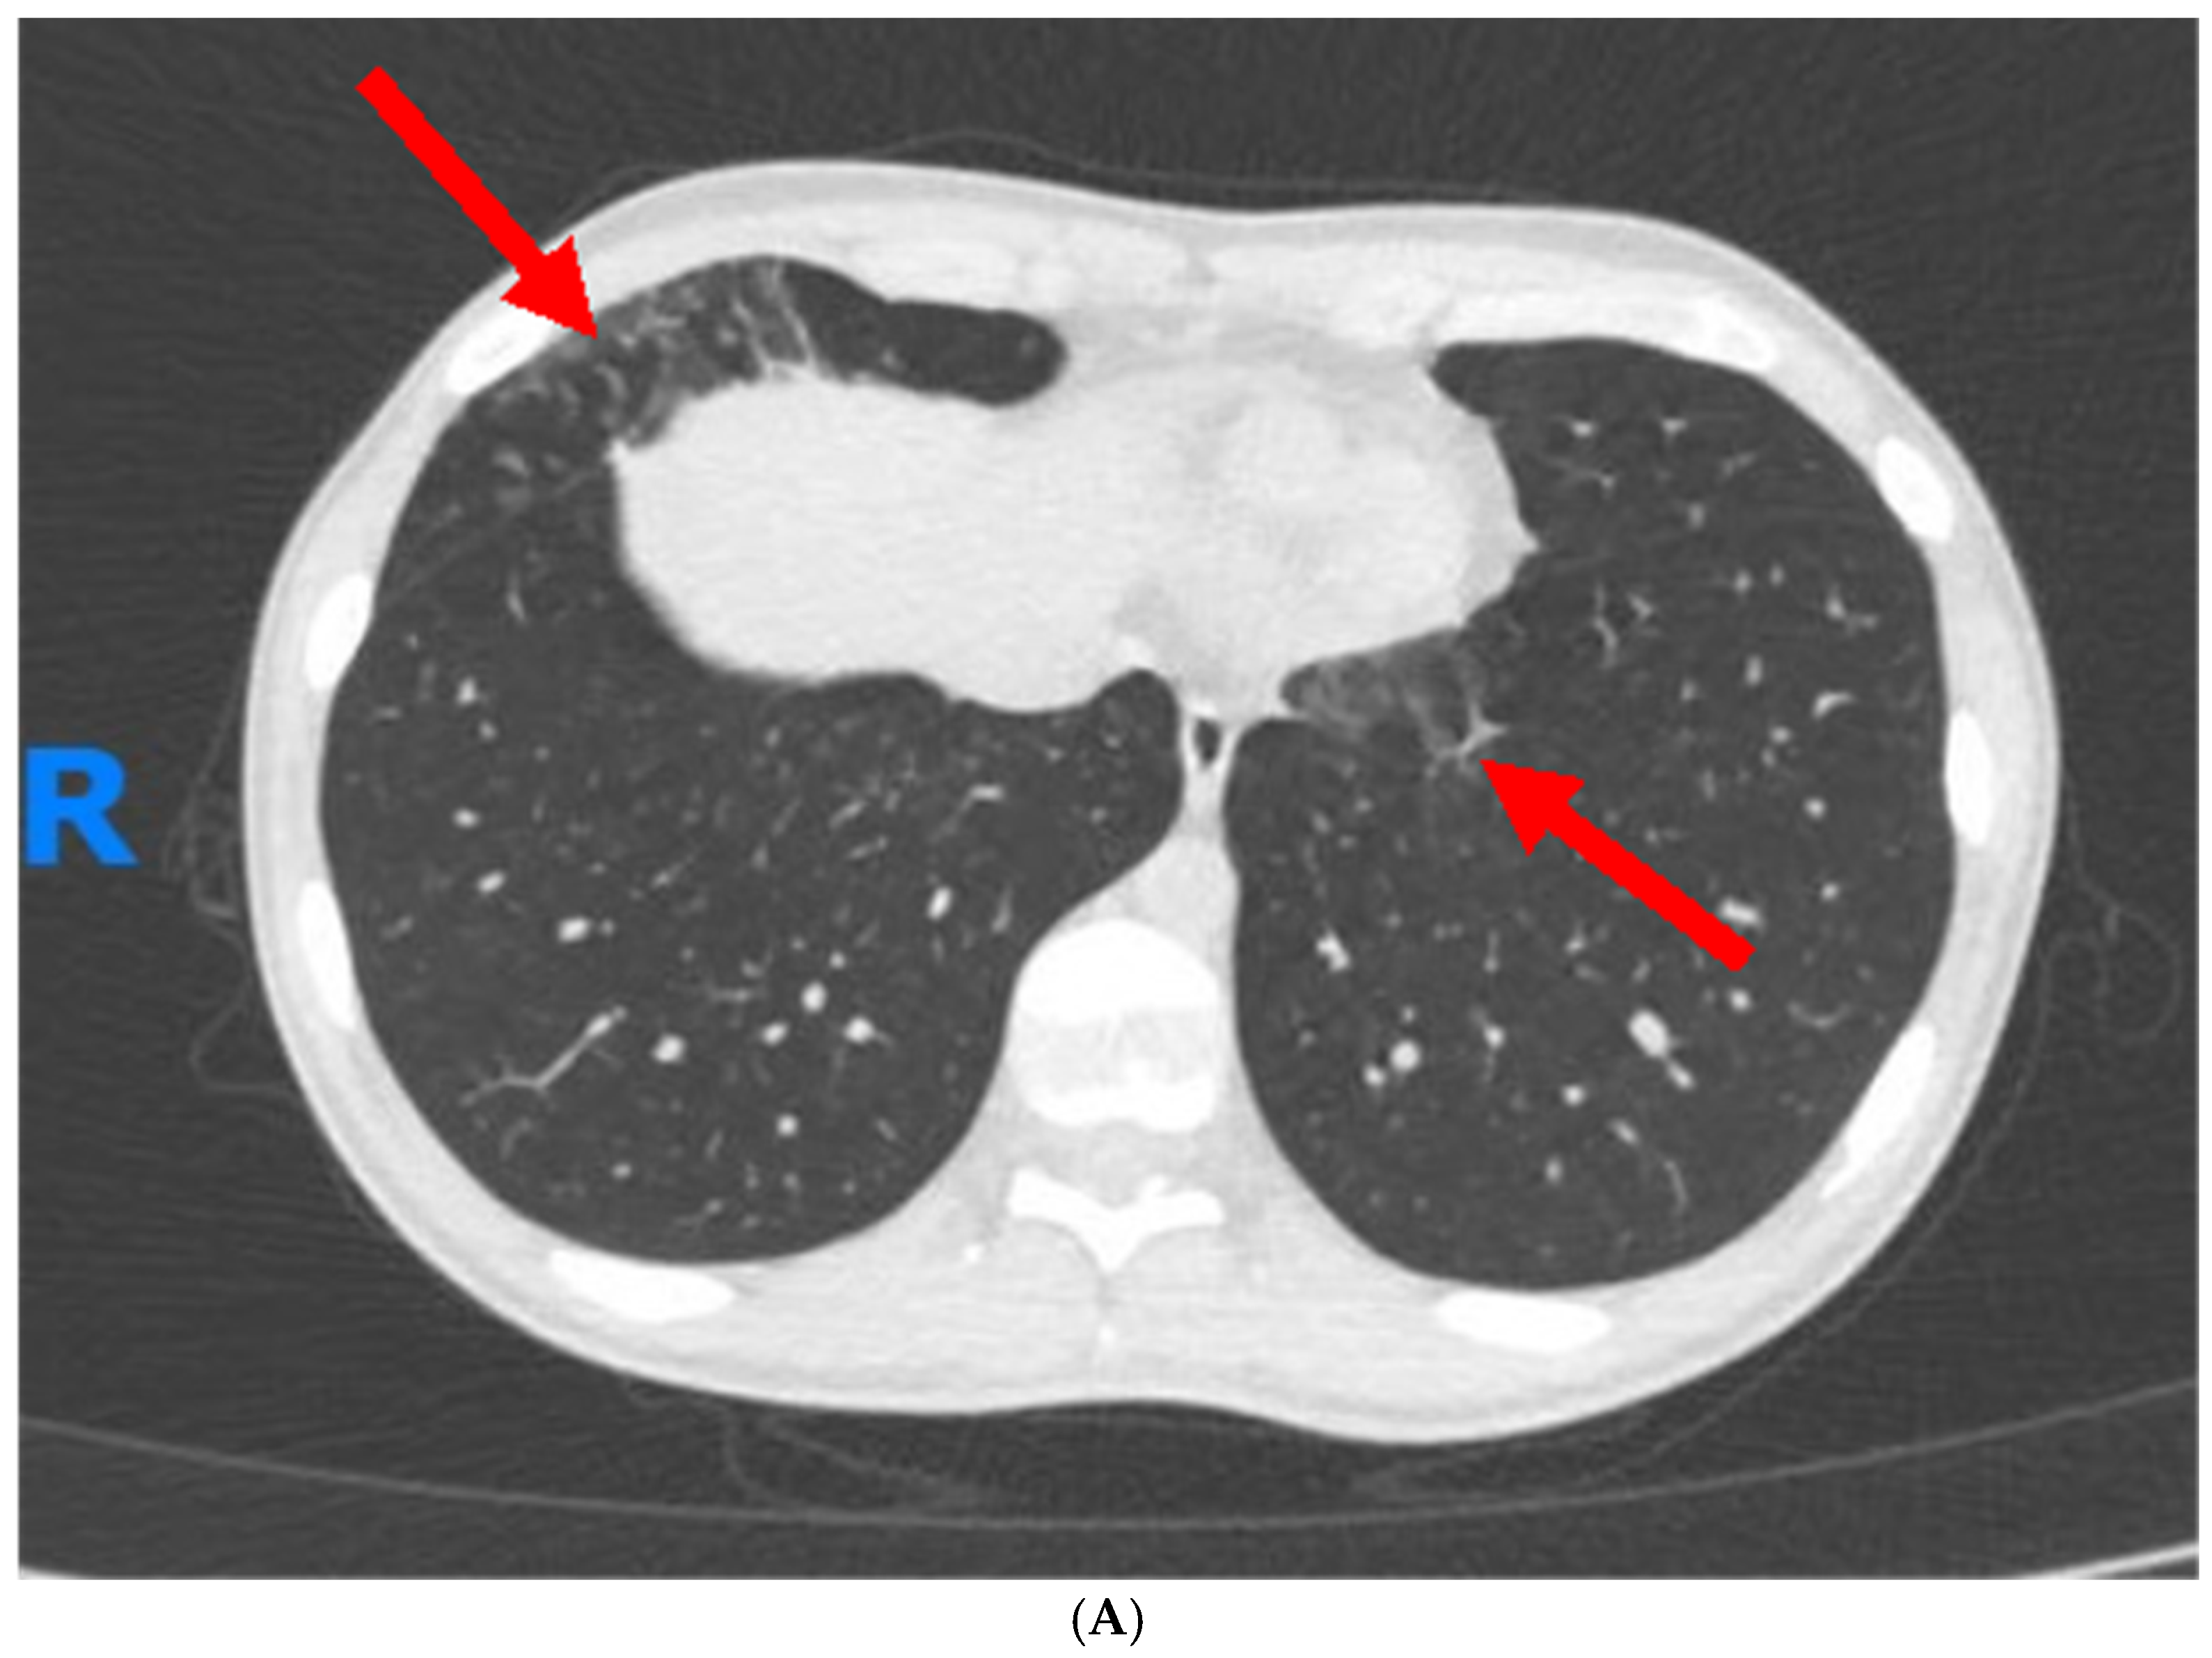

1. Case Report

| High-resolution computed tomography | More sensitive than X-ray, can identify features such as bronchial wall thickening, airway dilation, and mucoid impaction that are indicative of bronchiectasis, tree-in-bud patterns, ground-glass opacities, or honeycombing indicative of fibrotic changes [74,75]. |